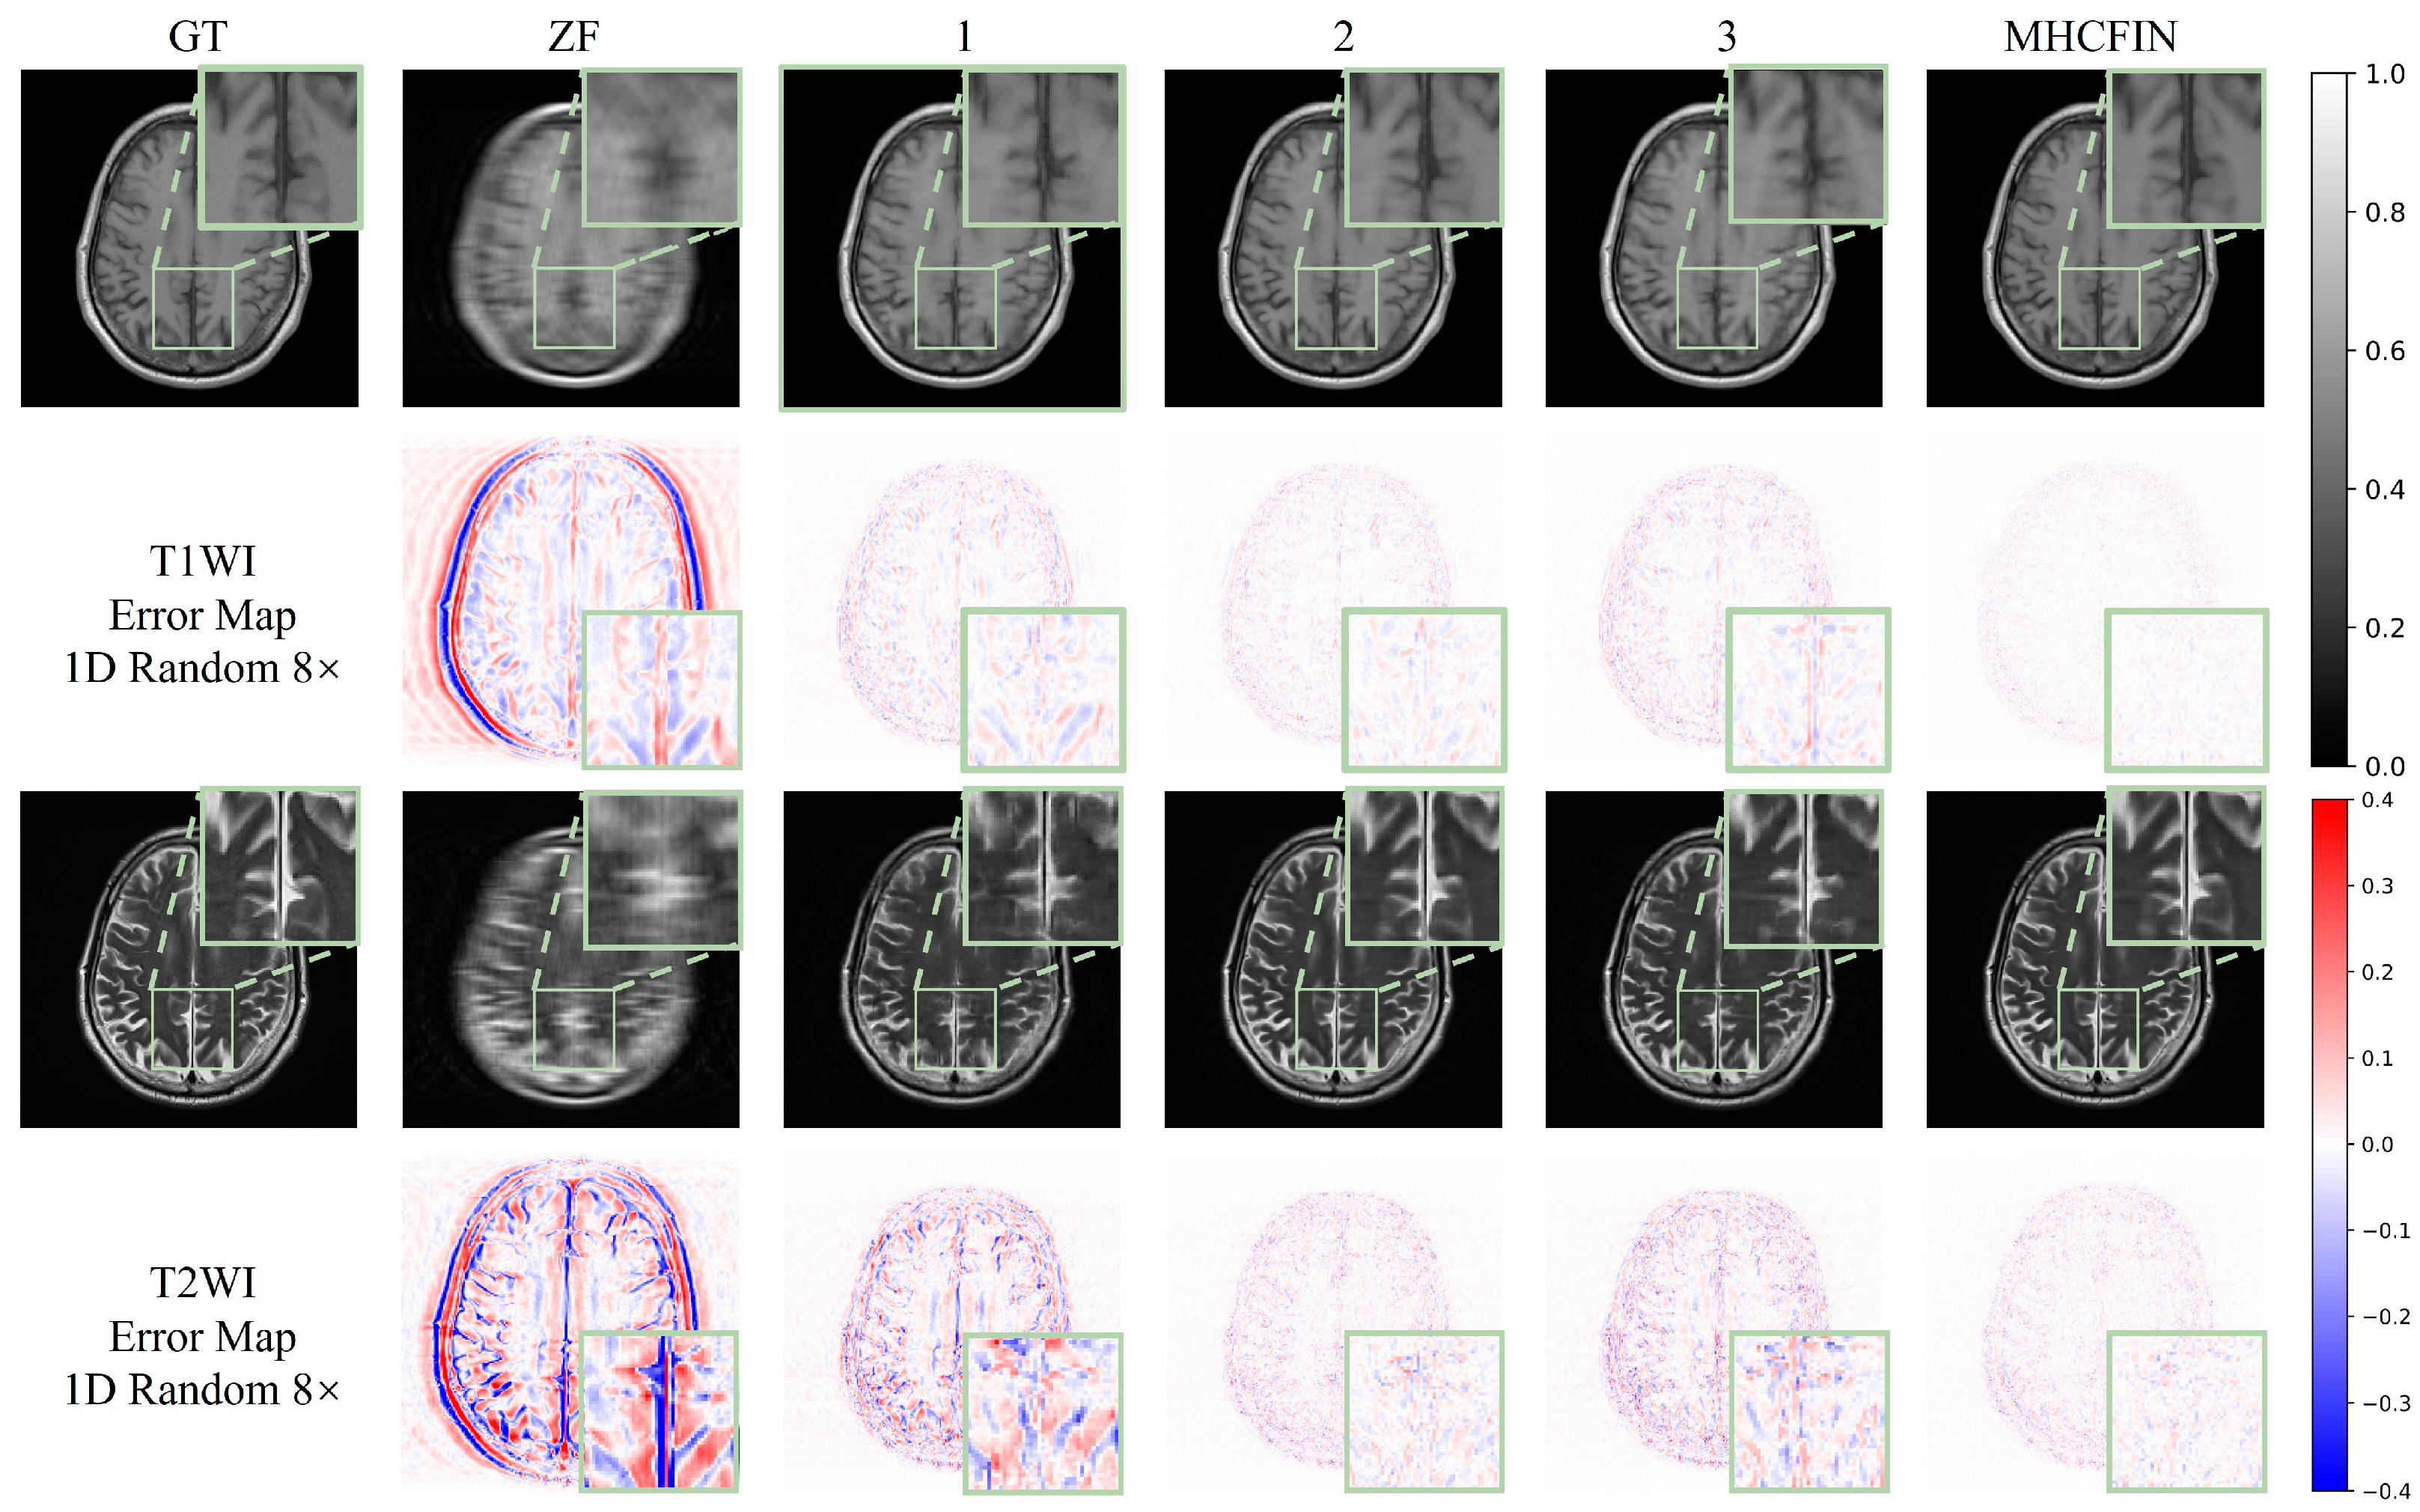

- Discussion on encoder and decoder based on residual multi-attention: To verify the efficacy of the key components in the proposed method, we evaluate three models in an ablation study. First, we evaluate the proposed residual multi-attention-based decoder–encoder model, in which we replace residual learning with traditional skip connections and remove the triple-attention mechanism. From the data in Table 4, we can see that, compared with configurations 1 and 2, without residual multi-attention (RMA), the PSNR of T1WI decreases by 2.974 dB and the SSIM decreases by 0.037; similarly, the PSNR of T2WI decreases by 5.964 dB and the SSIM decreases by 0.08. It can also be observed in Figure 12 that the reconstruction error of configuration 2 is reduced compared to configuration 1 which does not integrate any components, and the restored image details are clearer.

- Discussion on the multi-modal feature interaction module and single-modal feature fusion module: Since the multi-modal fusion interaction module and the single-modal feature fusion module are used jointly, we discuss their effects together in the ablation study. As can be seen from the data in Table 4, compared with configuration 1 without using these feature fusion technologies, configuration 3 has the PSNR of T1WI increased by 0.782 dB, SSIM increased by 0.005, and RLNE decreased with the help of multi-modal feature interactive learning by 0.006; the improvement of T2WI is more significant, as PSNR increases by 3.338 dB, SSIM increases by 0.052, and RLNE decreases by 0.052. Figure 12 also clearly shows that, after the introduction of MMFIM and SMFFM, the overall reconstruction error is reduced; especially, the improvement on T2WI is particularly obvious. Based on the introduction of RMA, the difference between MMFIM and SMFFM is particularly significant. By comparing configuration MHCFIN with configuration 2, it can be seen that the PSNR of T1WI has increased by 3.323 dB, and the PSNR of T2WI has increased by 2.01 dB. This result verifies the effectiveness of our proposed components, and when these components are used jointly, they can bring better results than when used alone. At the same time, learning complementary information between different modalities can also further improve the quality of reconstruction.